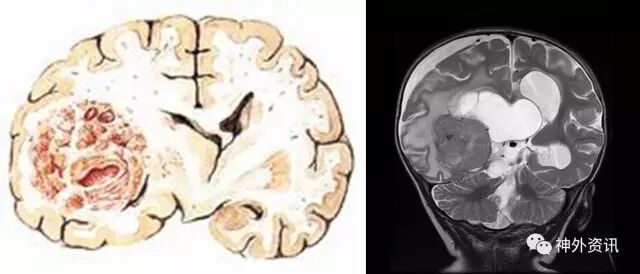

蛛网膜囊肿

1.蛛网膜囊肿是充满液体的先天性囊腔,边界由蛛网膜构成

2.大多数蛛网膜囊肿表现为静止状态

3.占位效应明显、引起临床症状的蛛网膜囊肿需要手术治疗

4.手术方法:内镜下造瘘、囊肿剥离术、囊肿-腹腔分流术